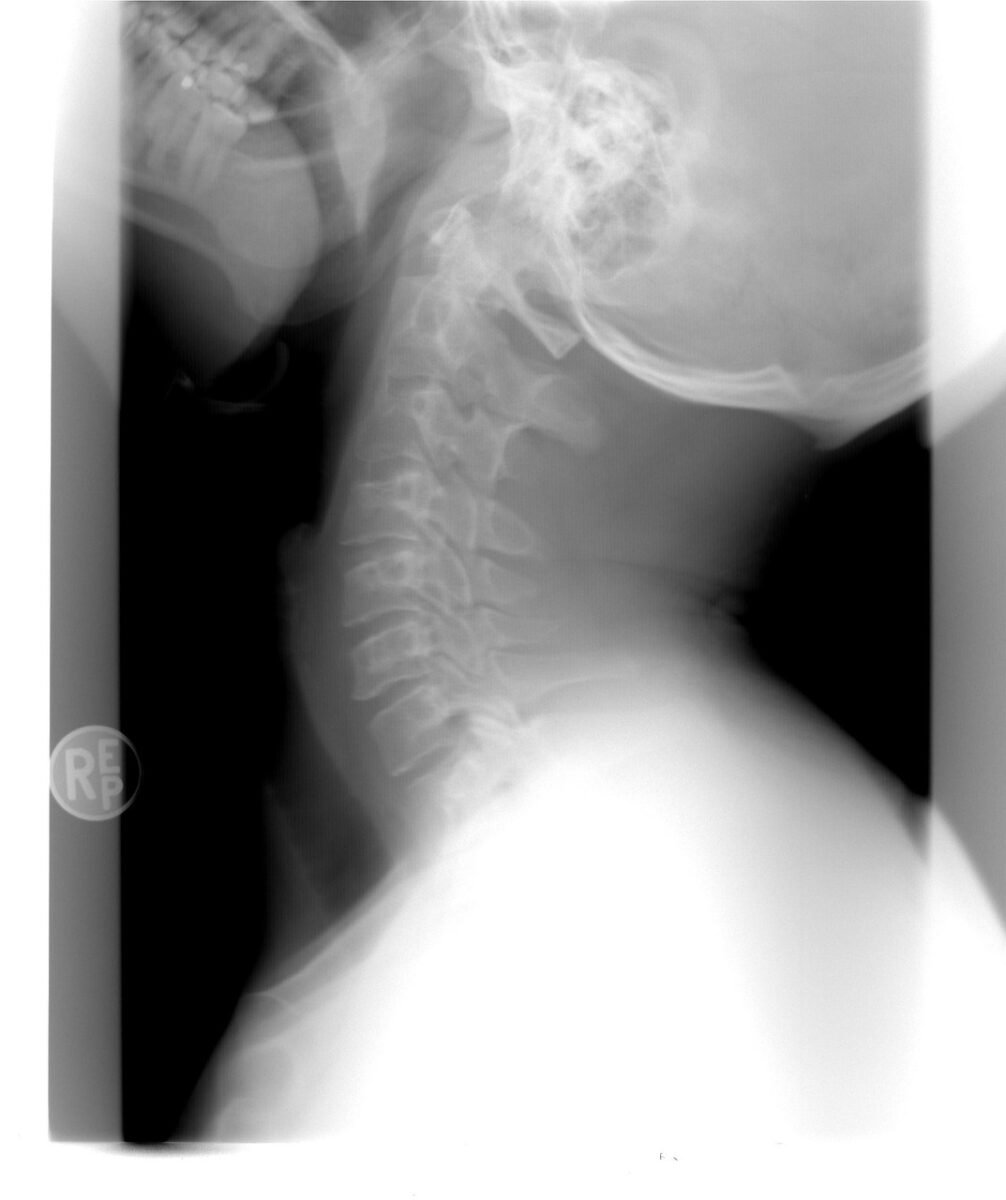

- Imaging studies: MRI of the cervical spine (and CT/X-ray if required) to confirm disc herniation, stenosis, or instability.

- Fusion monitoring: Follow-up X-rays are done to assess bone healing and implant position.